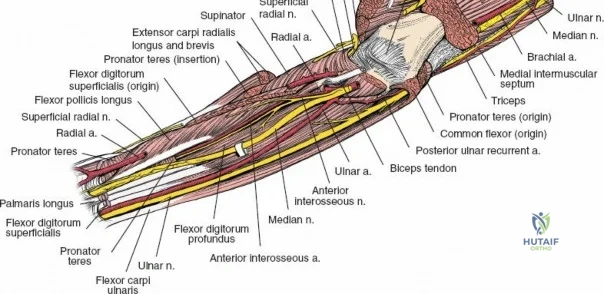

The anterior approach to the radius is an elegant example of utilizing true internervous planes to achieve deep exposure without denervating musculature. Distally, the internervous plane lies between the brachioradialis muscle (innervated by the radial nerve) and the flexor carpi radialis muscle (innervated by the median nerve). Proximally, the plane transitions to lie between the brachioradialis (radial nerve) and the pronator teres muscle (median nerve). Exploiting this plane allows the surgeon to mobilize the entire lateral muscular compartment (the "mobile wad" comprising the brachioradialis, extensor carpi radialis longus, and extensor carpi radialis brevis) away from the anterior flexor compartment.

Vascular Anatomy and the Recurrent Radial Leash

The radial artery runs distally through the forearm, initially lying deep to the brachioradialis muscle before becoming more superficial in the distal third. Just distal to the elbow joint, the radial artery gives off a complex network of vessels known as the recurrent radial artery leash (the "leash of Henry"). These vessels branch laterally to supply the brachioradialis and the mobile wad. To successfully mobilize the brachioradialis laterally and access the proximal radius, this entire leash of vessels must be meticulously isolated, ligated, and divided. Failure to do so will tether the brachioradialis, prevent adequate exposure, and risk severe postoperative hematoma from avulsed vessels.

Incise the deep fascia of the forearm in line with the skin incision. The initial goal is to identify the medial border of the brachioradialis as it courses down the forearm. It is a common pitfall to search for this border too far laterally. At the level of the elbow, the brachioradialis is expansive and extends almost halfway across the anterior forearm. It is surprisingly easy to mistake the plane between the brachioradialis and the extensor carpi radialis longus for the correct intermuscular plane.

To confirm the correct plane, look for the superficial branch of the radial nerve. This sensory nerve runs on the undersurface of the brachioradialis muscle. Once the true medial edge of the brachioradialis is found, develop the plane between it and the pronator teres (proximally) or the flexor carpi radialis (distally). Retract the brachioradialis laterally, taking care to keep the superficial radial nerve attached to its undersurface to protect it from traction injury.

Managing the Radial Artery and Recurrent Leash

As the brachioradialis is retracted laterally, the radial artery and its venae comitantes are exposed lying deep in the middle part of the forearm, closely related to the medial edge of the wound. Begin dissection distally and work proximally. Just below the elbow joint, the radial artery gives off the recurrent radial artery and a leash of muscular branches that dive laterally into the brachioradialis.

This leash must be meticulously managed. Take time to isolate, ligate, and divide these vessels. Do not attempt to use electrocautery alone on the larger branches, and absolutely avoid blunt avulsion. Avulsion of these vessels from the main radial artery is a potent cause of difficult-to-control intraoperative bleeding and severe postoperative hematoma. Once the leash is divided, the brachioradialis can be fully mobilized laterally, exposing the deep muscular layer.

Exposing the proximal third of the radius requires extreme vigilance due to the proximity of the posterior interosseous nerve. The key anatomical landmark here is the insertion of the biceps tendon. Follow the biceps tendon distally to its insertion on the bicipital tuberosity of the radius. A small bursa lies just lateral to the tendon; incise this bursa to gain initial access to the proximal radial shaft. Because the radial artery lies superficial and medial to the tendon at this level, all deep dissection must remain strictly lateral to the biceps tendon.

The proximal radius is draped by the supinator muscle. The PIN passes directly through the belly of the supinator. To protect the nerve, the forearm must be fully supinated. Supination dynamically rotates the radius, carrying the insertion of the supinator anteriorly and simultaneously displacing the PIN laterally and posteriorly, safely away from the surgical field.